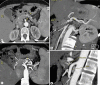

We describe a case of clinical benefit and partial response with gemcitabine and oxaliplatin (GEMOX) in a young patient with ovarian metastasis from cystadenocarcinoma of the pancreas. A young woman complained of abdominal pain and constipation. Computed tomography (CT) and magnetic resonance imaging scans disclosed two bilateral ovarian masses with pancreatic extension. She underwent bilateral ovarian and womb resection. During surgery peritoneal carcinosis, a pancreatic mass and multiple abdominal lesions were found. The final diagnosis was mucinous pancreatic cystadenocarcinoma with ovarian and peritoneal metastases. She started chemotherapy with GEMOX (gemcitabine 1,000 mg/m(2)/d1 and oxaliplatin 100 mg/m(2)/d2 every 2 weeks). After 12 cycles of chemotherapy a CT scan showed reduction of the pancreatic mass. She underwent distal pancreatic resection, regional lymphadenectomy and splenectomy. Pathologic examination documented prominent fibrous tissue and few neoplastic cells with mucin-filled cytoplasm. Chemotherapy was continued with gemcitabine as adjuvant treatment for another 3 cycles. There is currently no evidence of disease. As reported in the literature, GEMOX is associated with an improvement in progression-free survival and clinical benefit in patients with advanced pancreatic cancer. This is an interesting case in whom GEMOX transformed inoperable pancreatic cancer into a resectable tumor.